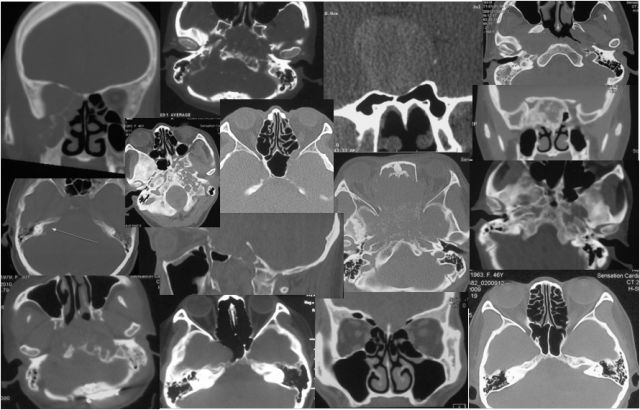

内镜经鼻蝶切除垂体瘤

术前

术后

内镜经鼻蝶切除颅咽管瘤